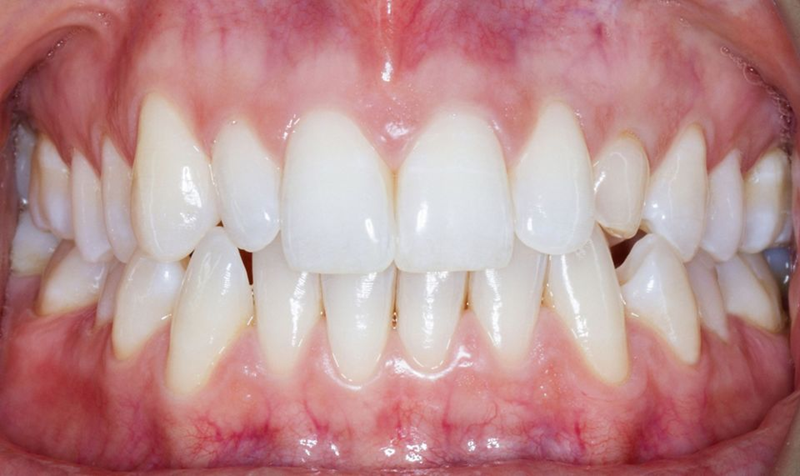

口内检查中,乳牙处可见大量角质化牙龈,整体口腔卫生状况良好(图5-7)。

Fig. 5: Intraoral frontal view

Fig. 6: Intraoral view: The discrepancy between upper canines and lateral incisors is clear. Note that the deciduous tooth is shorter than the contralateral, both at the occlusal and at the gingival side.

Fig. 7: Magnification of the deciduous tooth: A wide amount of keratinized gingiva is shown.